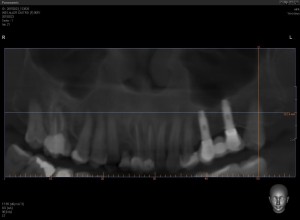

pano de tac